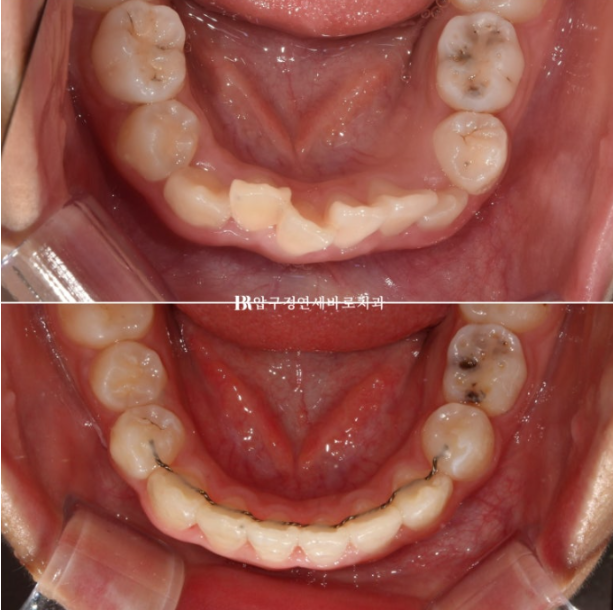

배열은 상당히 가지런해졌고 그 사이 유치가 여러개 빠지며 영구치가 내려오는 중입니다.

그렇게 5개월간 마지막 장치를 잘때만 끼면서 쉬는 시간을 가지다가 5개월 후 송곳니와 작은어금니가 어느정도 나와서 재제작에 들어갔습니다.

보증기간이 끝나기 직전에 17개월 차 쯔음 재제작을 한 번 더 하여 약간 돌아가있는 송곳니까지 완전히 배열을 마친 후 24년 8월에 드디어 치료를 종료했습니다.

재제작 총 2번 했고 토탈치료기간은 2년 중간에 쉬는 시간은 5개월 이었습니다.

치료 종료 시점 유치는 2개가 남아있었고 공간이 충분하여 아직 나오지 않은 계승영구치도 예쁘게 내려올 것으로 예상이 됩니다.

소아교정이여도 결과 유지를 위해서 유지장치가 필수입니다.

22.08~24.09